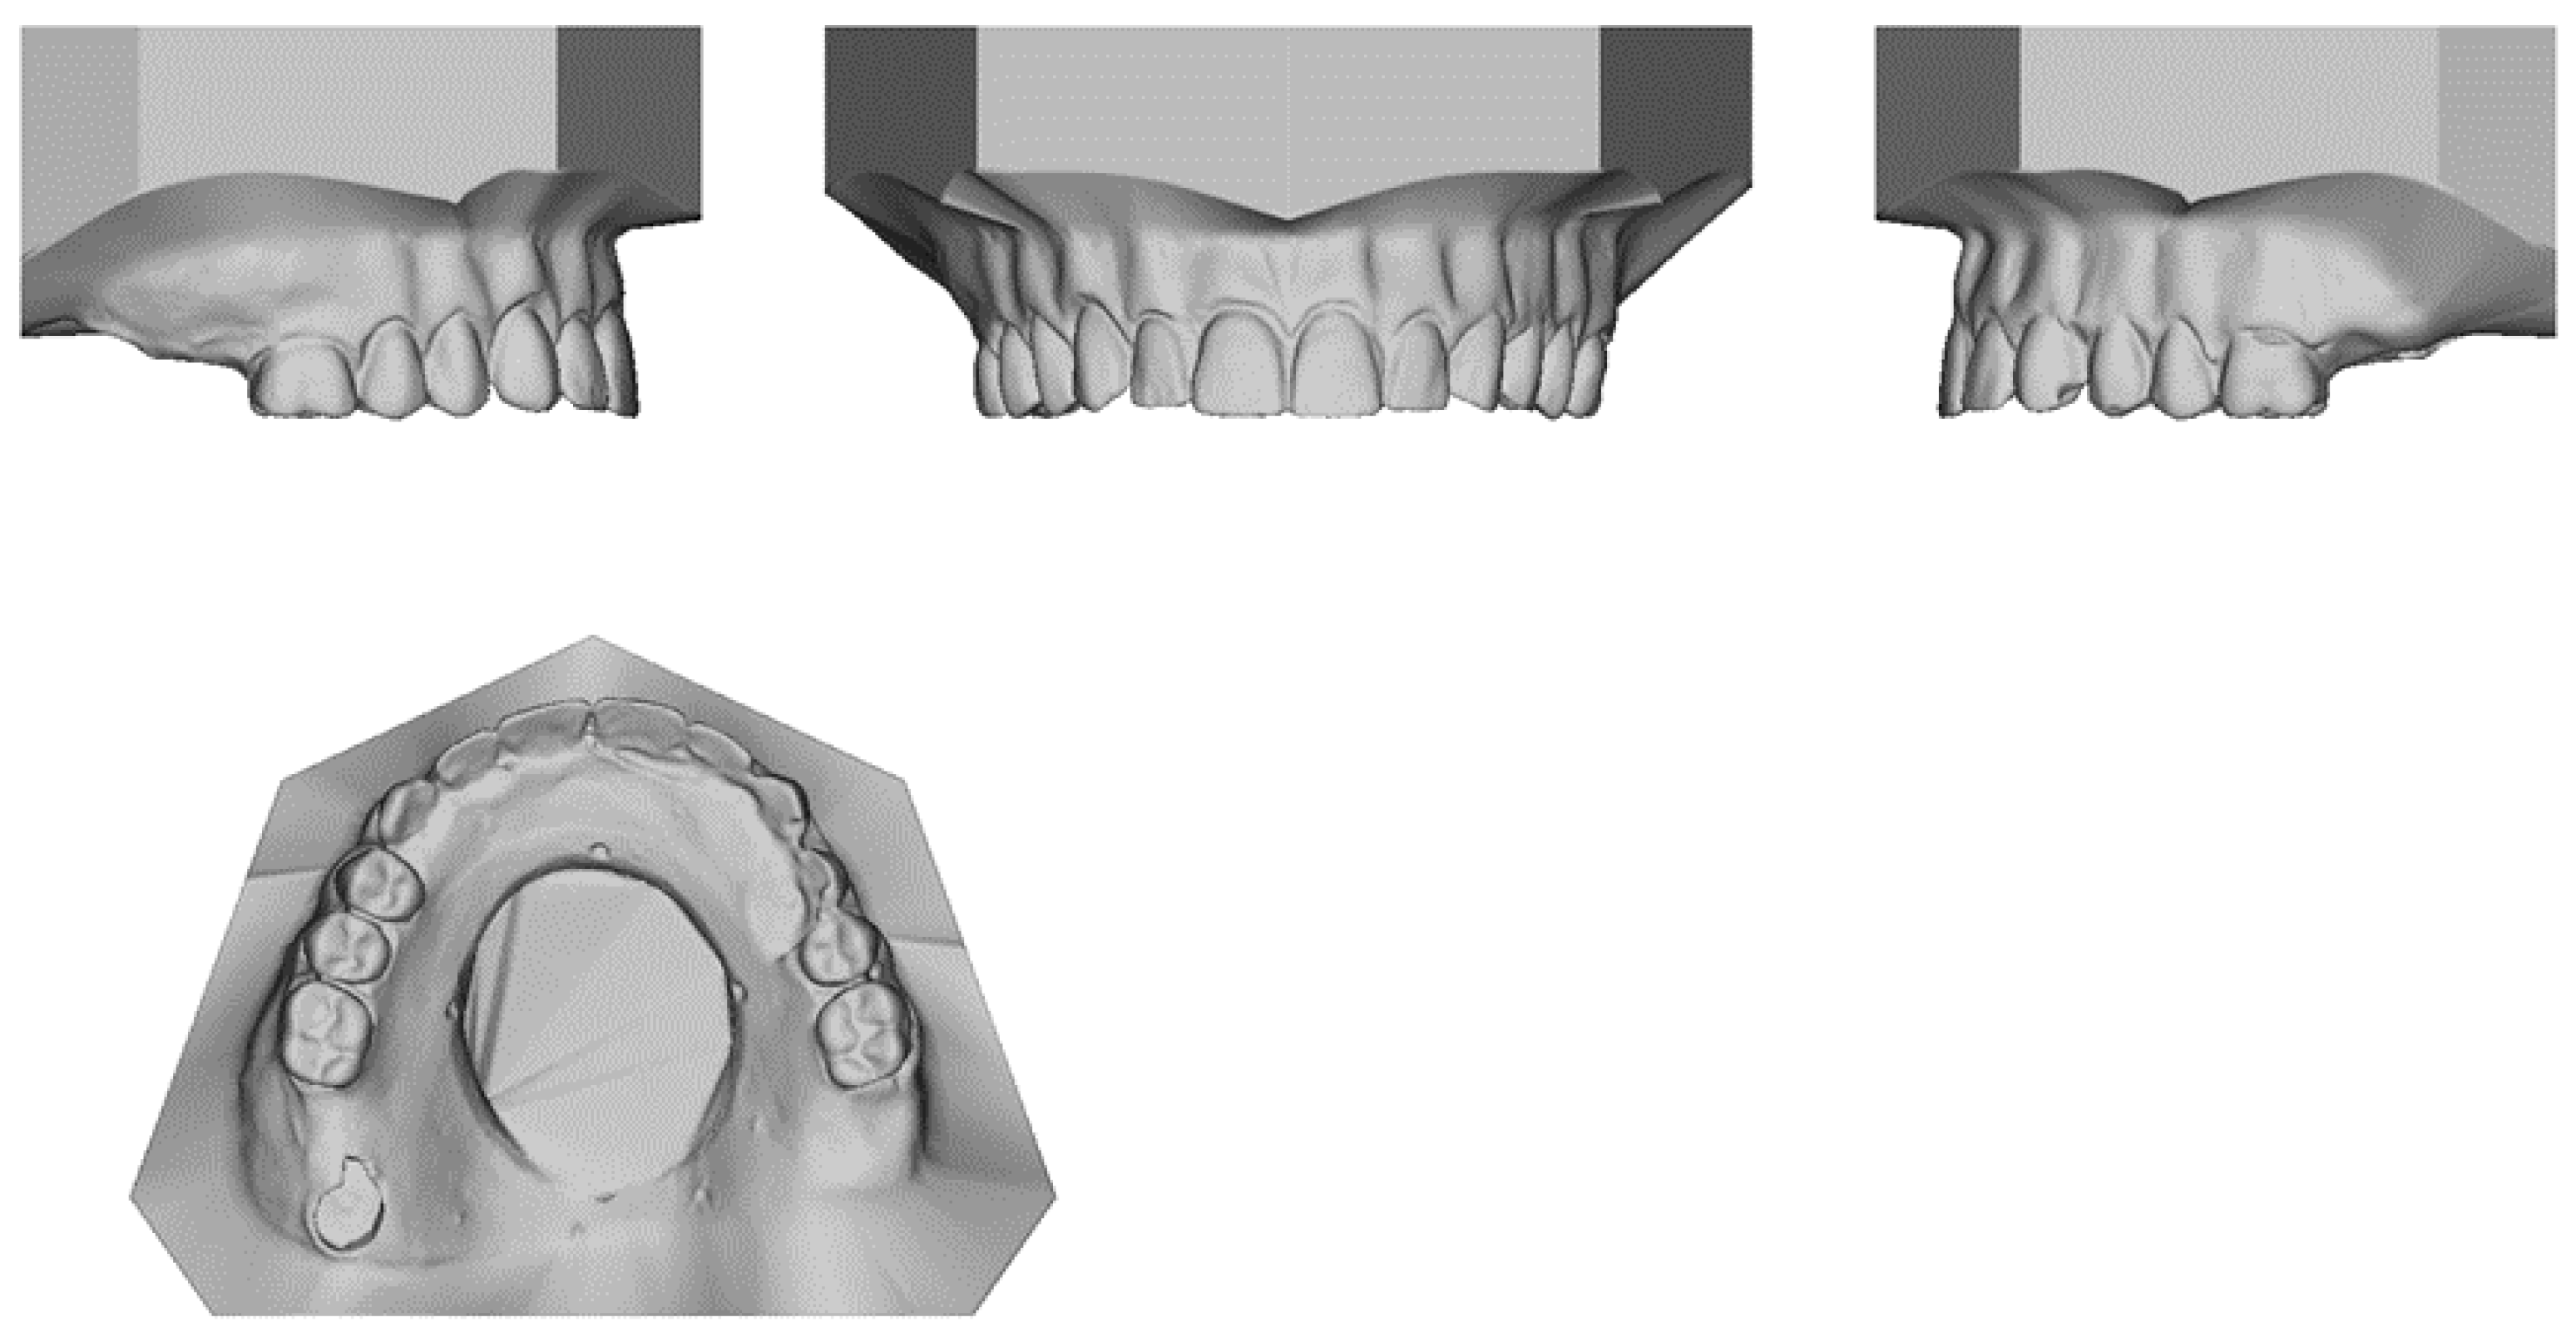

2.1. Defect Model Fabrication

2.2. Sample Fabrication for Comparison Experiments

2.2.1. Conventional Impression Technique

2.2.2. Digital Technique